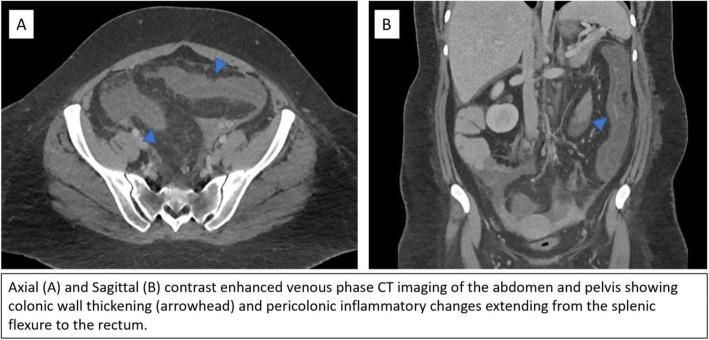

This report describes a 24-year-old female patient with findings of colitis and an abnormal arteriovenous connection of the inferior mesenteric arterial and venous systems. Partial embolization of this arteriovenous connection temporarily improved the patient's condition, but her symptoms ultimately returned due to the presence of multiple smaller feeder vessels not amenable to embolization, necessitating colonic resection for definitive treatment. Although prior reports have hypothesized that arterial pressurization of the veins may precipitate myointimal hyperplasia, to the authors' knowledge, this is the first report of IMHMV with an associated abnormal arteriovenous connection.